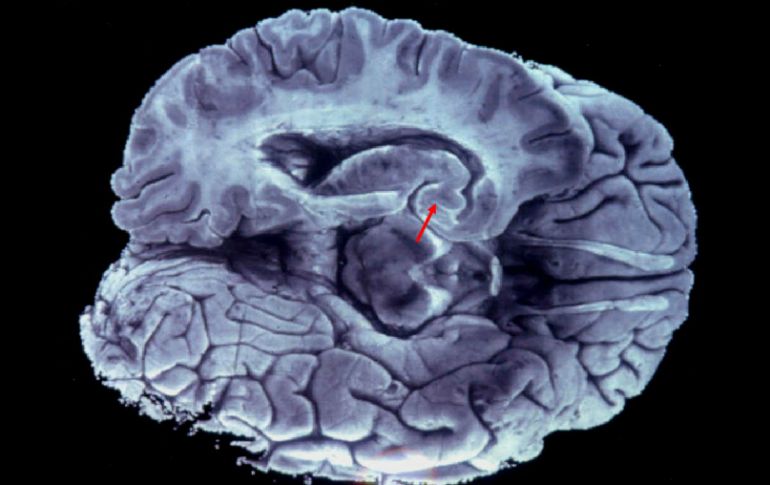

El lóbulo9 frontal está al mando del cerebro, pero situaciones como las señaladas, reducen su eficiencia. EFE / ARCHIVO

CIUDAD DE MÉXICO (17/MAR/2016).- Las alucinaciones auditivas y visuales son más frecuentes de lo que pudiera pensarse, y para que ocurran no se necesita algún tipo de sustancia, sino una falla entre el lóbulo frontal y la corteza cerebral.

John McGrath, especialista del Queensland Brain Institute, señaló que en ocasiones algo va mal en la relación lóbulo frontal-corteza cerebral, y se genera la falla de percepción o alucinación, publicó la Australian Broadcasting Corporation (ABC).

Puntualizó que cuando todo va bien, el lóbulo frontal está al mando y controla al conjunto del cerebro, pero situaciones como las señaladas, reducen su eficiencia y es cuando se puede crear la alucinación.